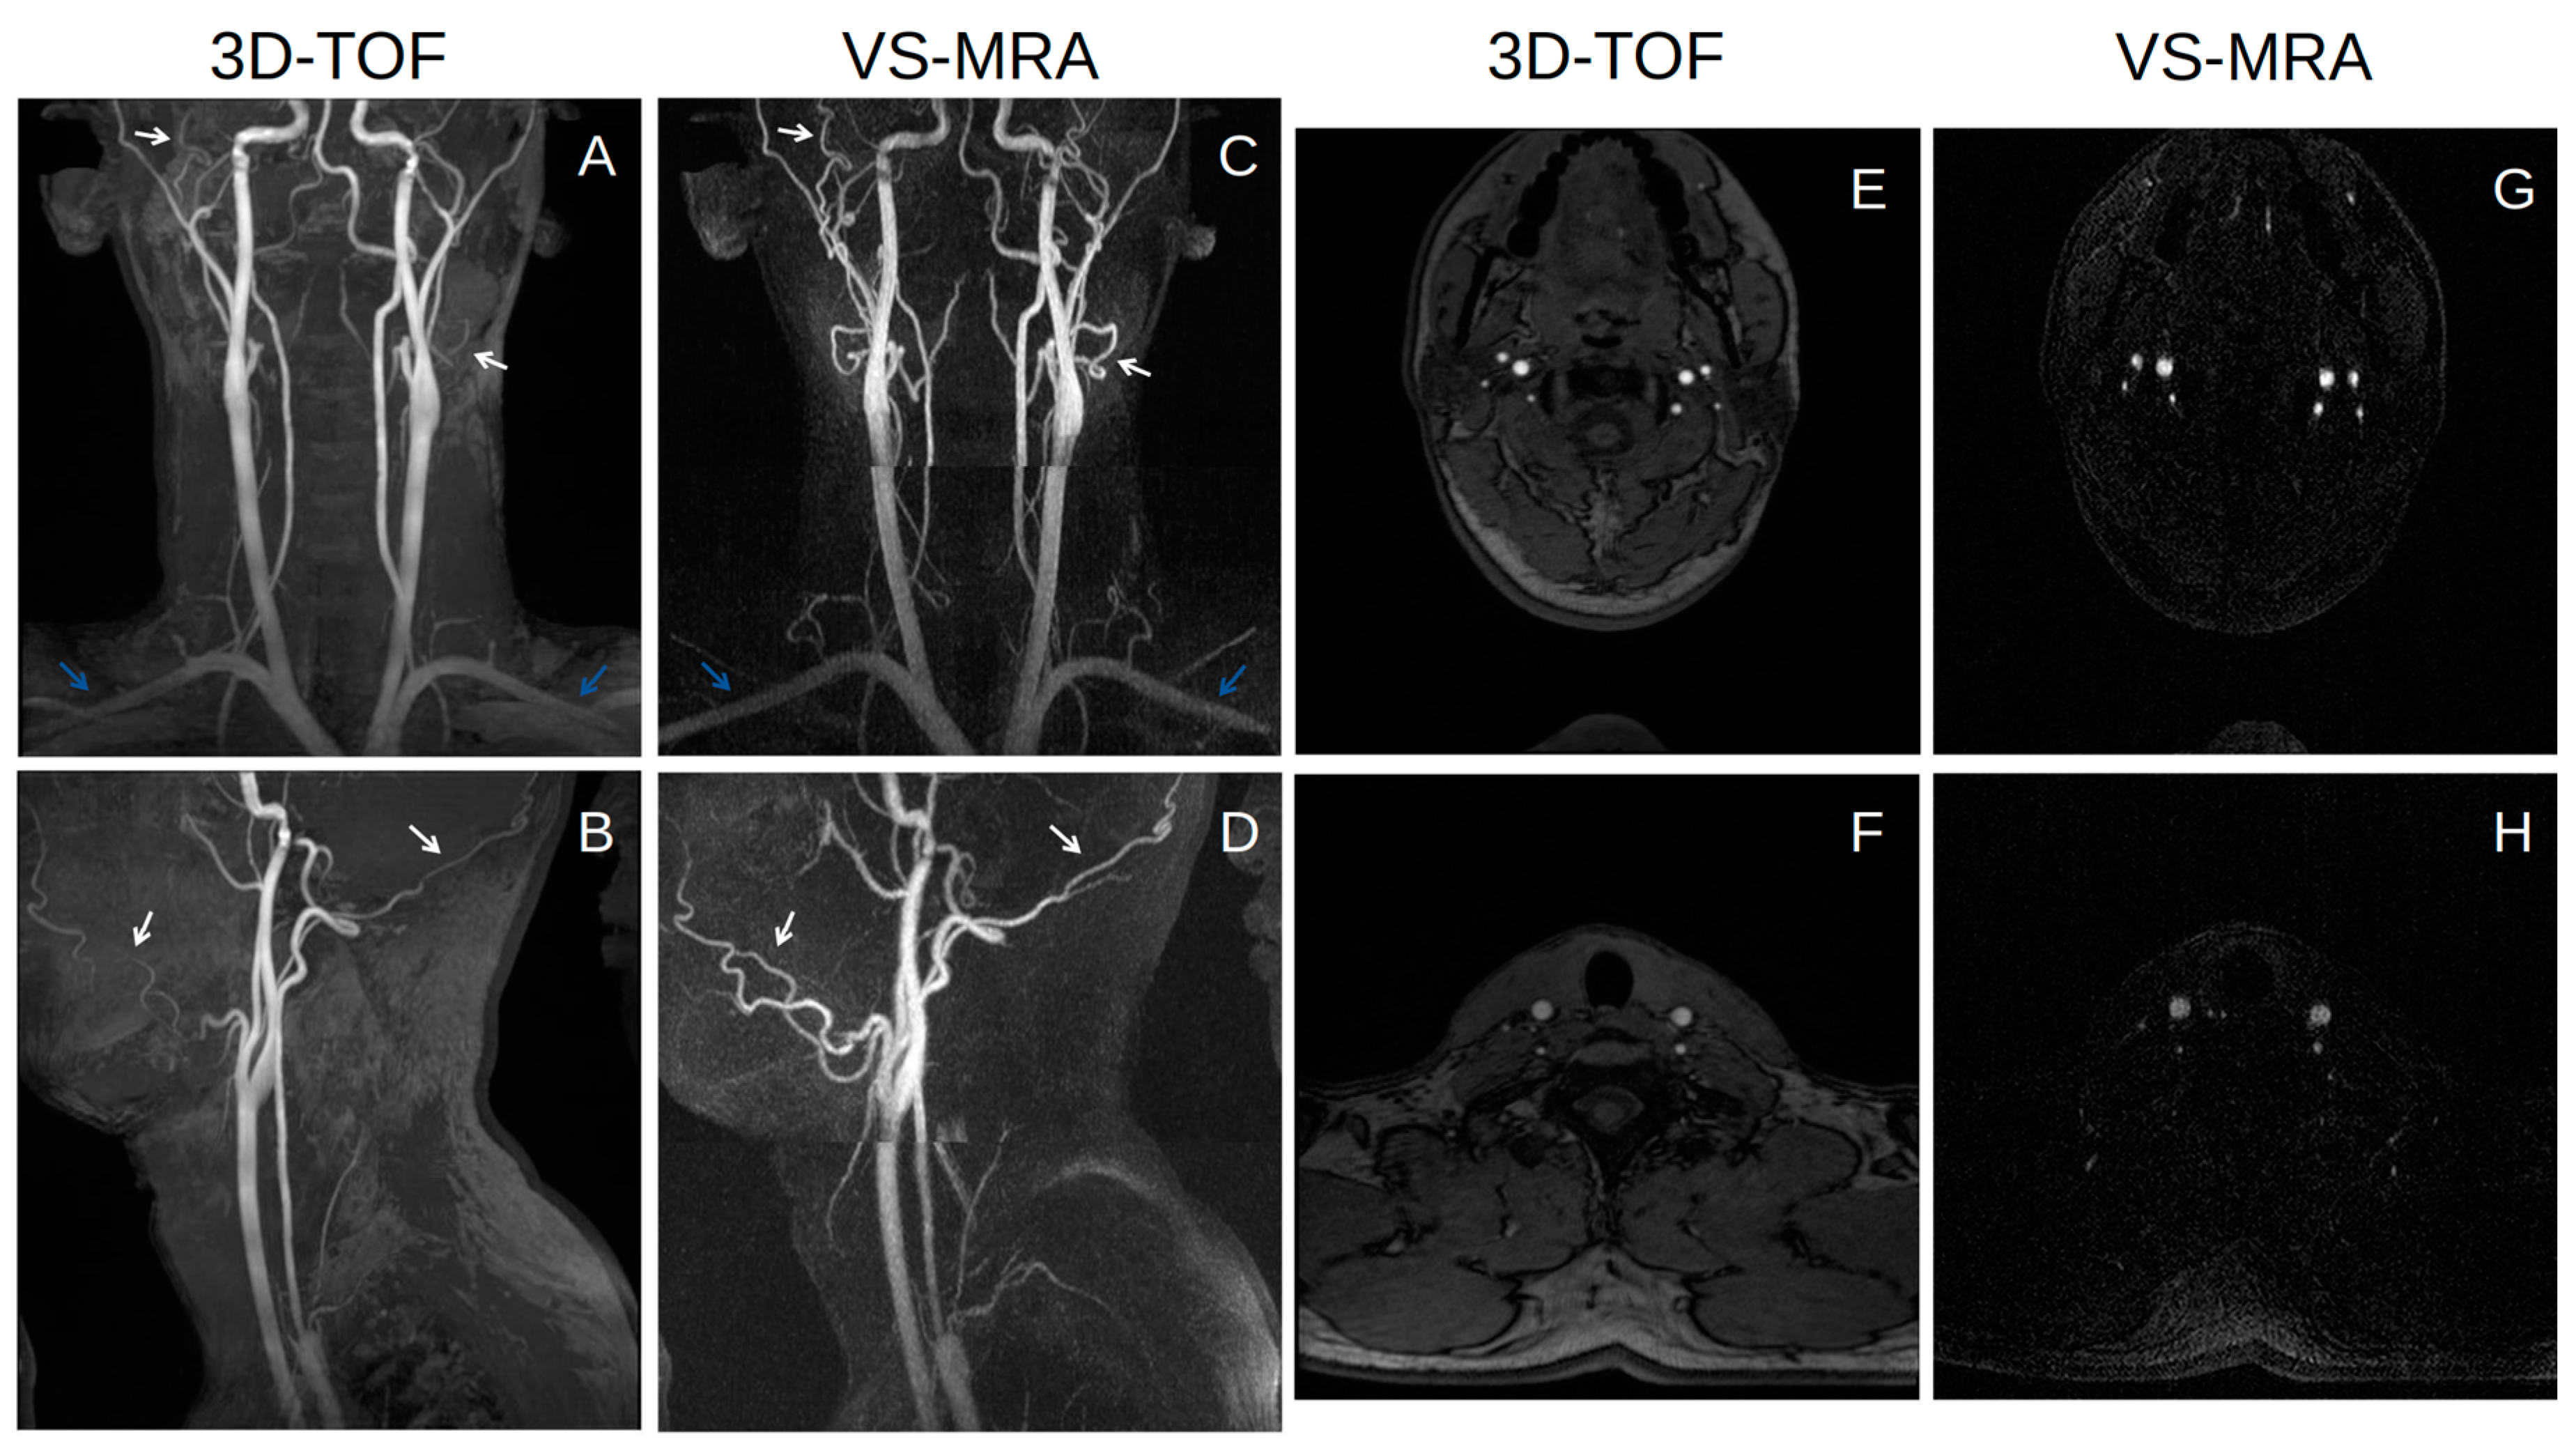

3.2. Neck MRA Experiments